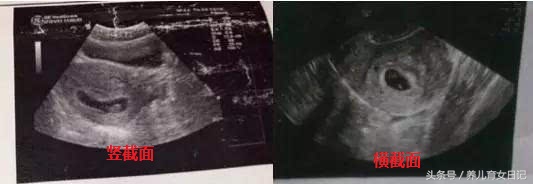

首先仅限8周之前的B超单,40多天是最合适的,然后就是要有3个数据的,如果没有3个数据的,一律不能判断,因为孕囊都是圆柱状的,可是B超师做B超的时候,截面会截取的方位不一样,有的横截面,有的截取竖截面,所以,看图片是长的还是圆的,不能判断男女。

比如B超单上是4.0cm*4.0cm*2.0cm,那肯定是男孩,但是如果B超师横截面时,孕囊就成了4.0cm*4.0cm的两个数据,看上去就是圆的了,然后造成了,孕囊是圆的,结果怎么生出了儿子,貌似不准的误导。